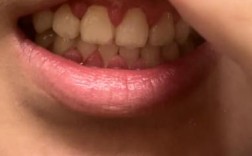

轻度增生

- 临床表现:牙龈边缘轻微圆钝,呈淡红色或鲜红色,探诊易出血,但未超过牙面1/3,无明显疼痛,对口腔清洁和美观影响较小。

- 图片特征:牙龈缘略增厚,与牙齿之间可见清晰的龈沟,表面光滑,无颗粒感,刷牙或使用牙线时少量出血(图片中可见牙龈缘轻微泛红,局部有点状出血痕迹)。